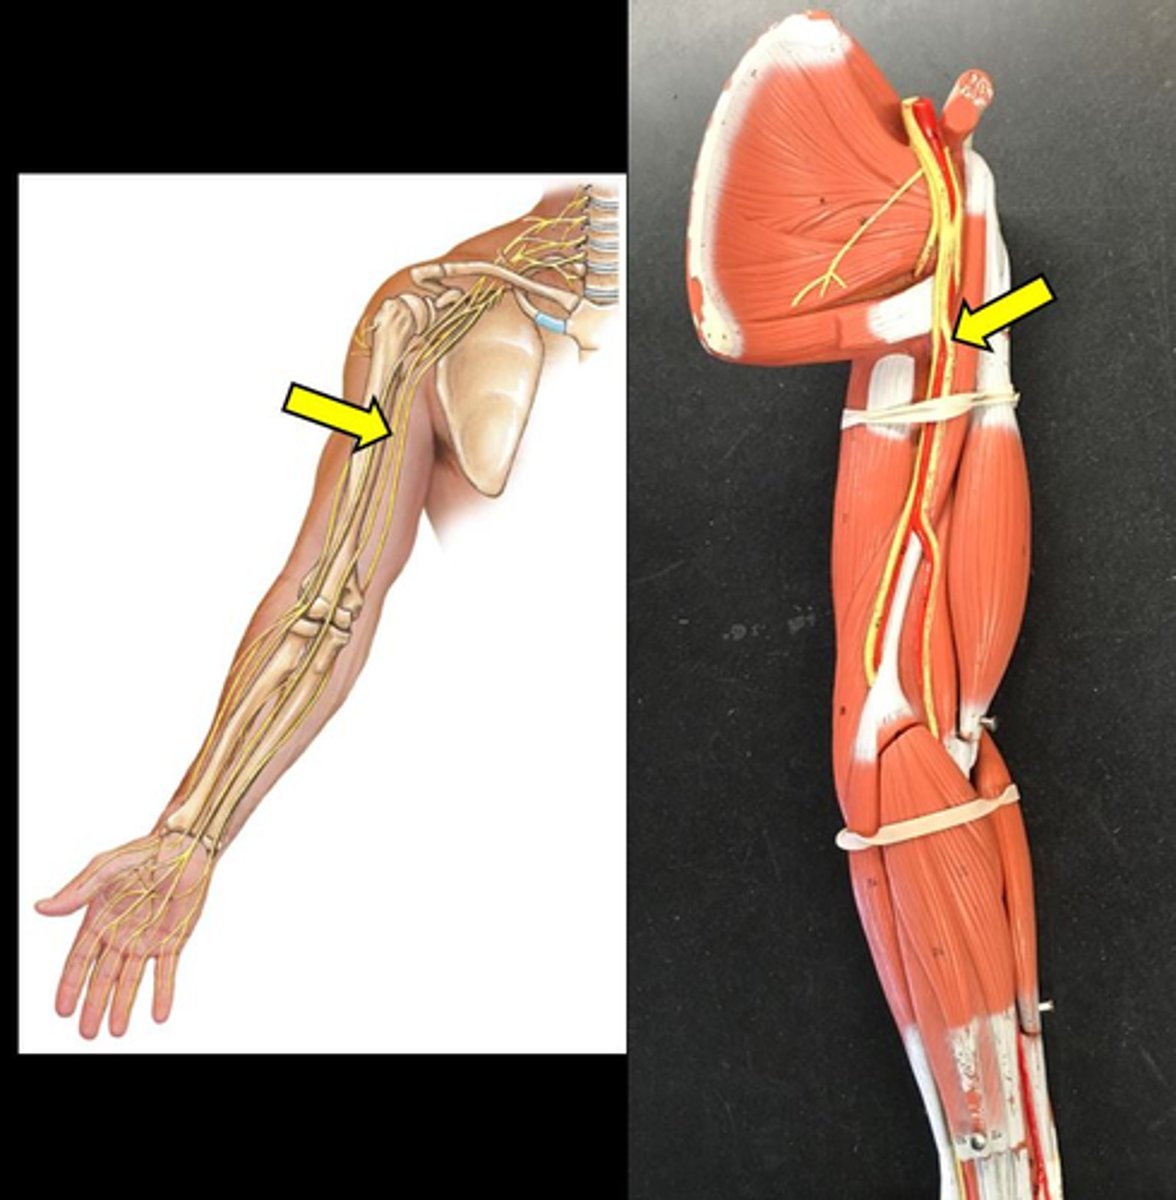

musculocutaneous nerve

median nerve

ulnar nerve

axillary nerve

dives deep near teres major

radial nerve

suprascapular nerve

Branches off the superior trunk

Seen on cadavers or picture

Subscapular nerve